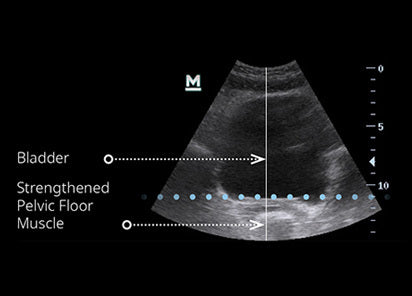

The Emsella Chair is a revolutionary, non-invasive treatment that uses high-intensity focused electromagnetic (HIFEM) technology to strengthen the pelvic floor muscles. One 28-minute session delivers the equivalent of over 11,000 Kegel exercises, helping improve bladder control, pelvic health, and overall confidence.